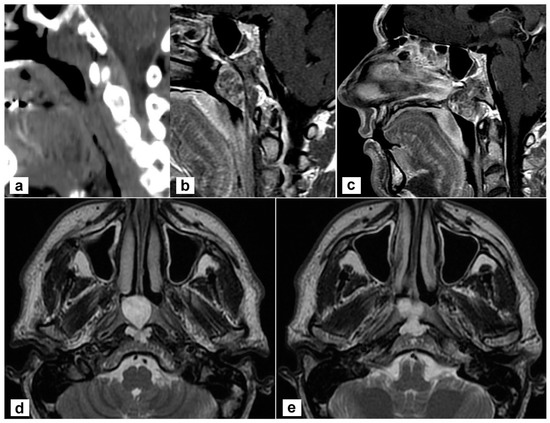

3.1. Case Presentation